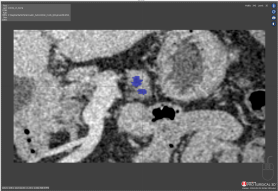

Scan 19: Overlap of 90.2

Overlap

Overlap is the area of the Ground truth and Test segmentations that cover the same area.